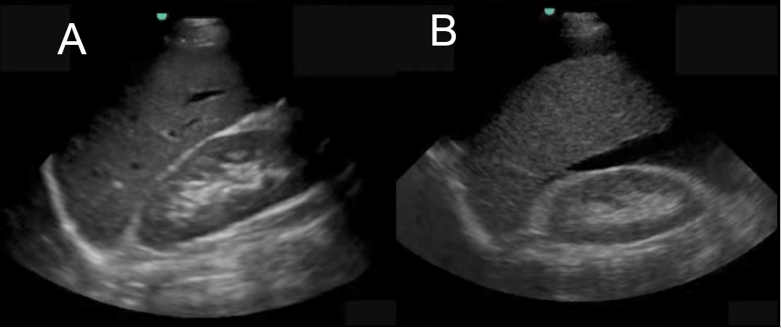

eFAST Right Upper Quadrant (RUQ) Image

A. No Fluid

B. Abnormal Fluid Collection